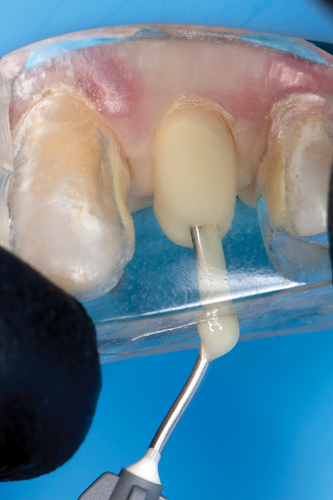

The clear silicone matrix was placed over the posterior segment of the maxillary arch, and an opacious A2-shaded injectable flowable universal resin composite was injected through a small opening above the preparation and fiber post (Figure 20 and Figure 21). The resin composite was cured through the clear resin matrix on the incisal, facial, and lingual aspects for 40 seconds each. Upon removal of the matrix, the excess polymerized composite resin was removed with a #12 scalpel blade, and the incisal sprue was removed using a tapered diamond finishing bur. A round, tapered diamond bur was used to establish the gingival margin (Figure 22) and a needle-shaped finishing bur was used to complete the finishing of the preparation.

Fig 20. The clear silicone matrix was placed over the posterior segment of the maxillary arch, and flowable resin composite was injected through a small opening above the preparation and fiber post.

Figure 20

Fig 21. During the injection process, the tip was removed slowly while injecting to prevent the incorporation of air bubbles.

Figure 21